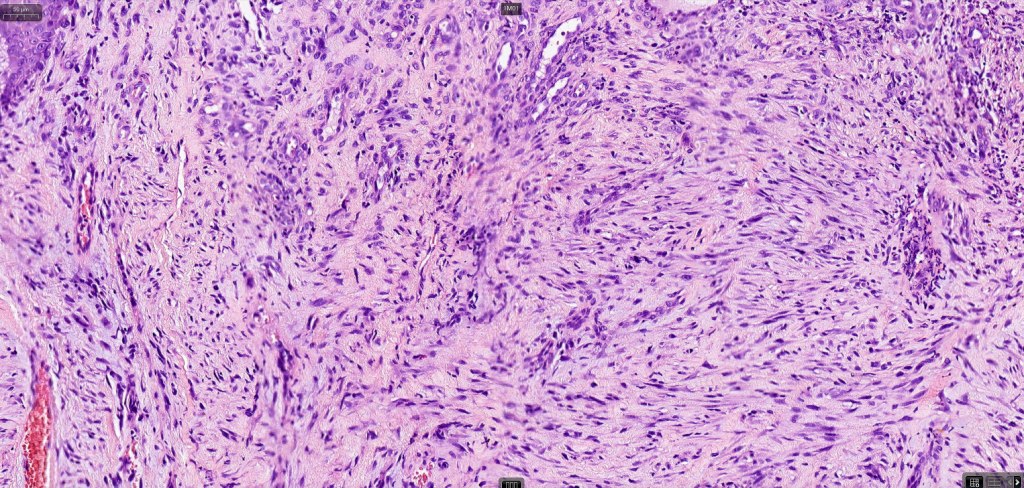

Histological features

•Paucicellular spindle cell infiltrate with “myxoid” fine to a dense collagenous stroma

•Hyperchromatic nuclei

•Variable pleomorphism

•Neurotropism

•Neural transformation

•Mixed desmoplastic & spindle cell variant (10%)